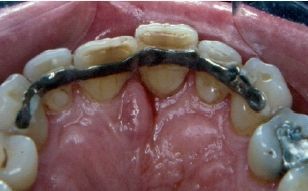

• Férulas exclusivamente de composite. Son fáciles de colocar, pero son muy frágiles y laboriosas a la hora de retirarlas. • Férulas de alambre de ortodoncia sujeto al diente con composite. Son fáciles de colocar, baratas, confortables para el paciente y fáciles de retirar. El alambre para ferulizar no se sujeta mediante brackets porque, en ese caso, existe mucho riesgo de que no sea pasivo y de que, inadvertidamente, se apliquen fuerzas ortodóncicas que dificultarían la reparación biológica.